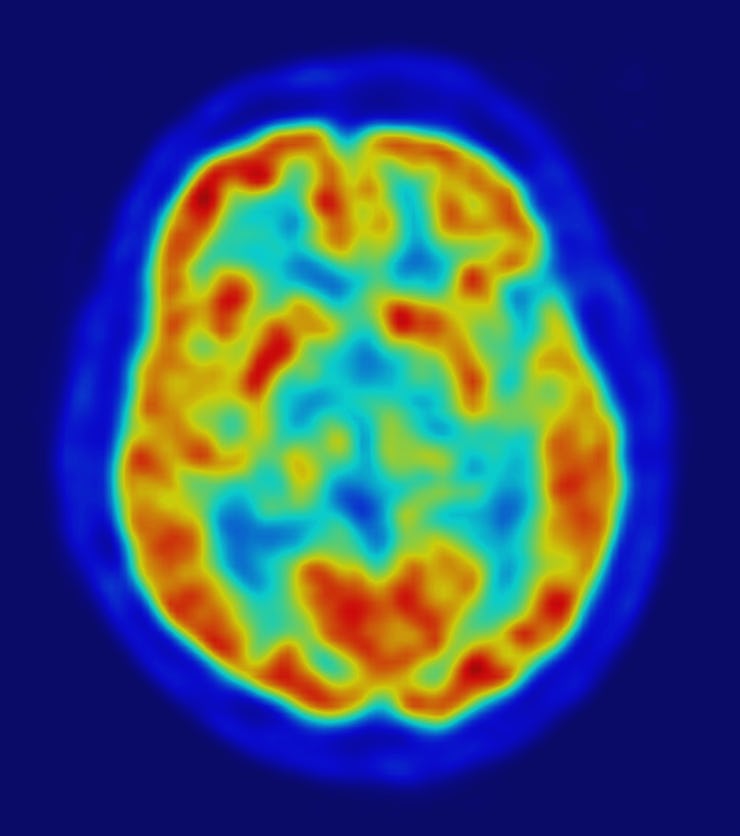

The brain on LSD shows higher resting state functional connectivity between the visual cortex and the rest of the brain.

This Is Your Brain on LSD

Last year a team of researchers published the first brain scans of people on LSD that use modern neuroimaging techniques. The results showed a surprisingly strong connection between how people experience an acid trip, and what is physically going on in their brains. Compared to a placebo group, participants on LSD had more blood flow to their visual cortex — the visual processing center — and way more connectivity between the visual cortex and the rest of the brain. The times when this activity was strongest was when people said they were experiencing visual hallucinations.